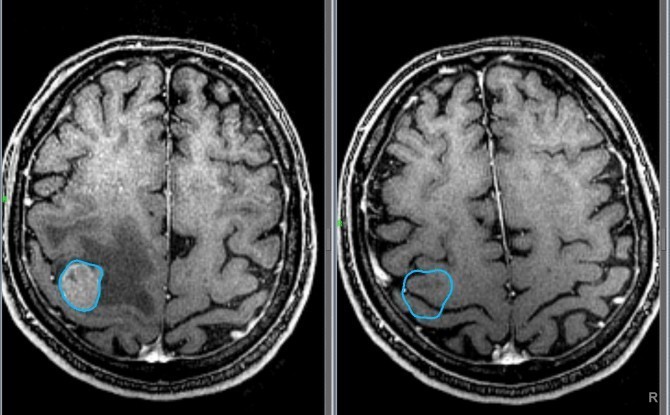

Общий анализ крови может также косвенно указывать на наличие опухоли. Если же имеются подозрения на наличие онкологии, то проводят следующие исследования:

- МРТ и КТ;

- биопсия опухоли.